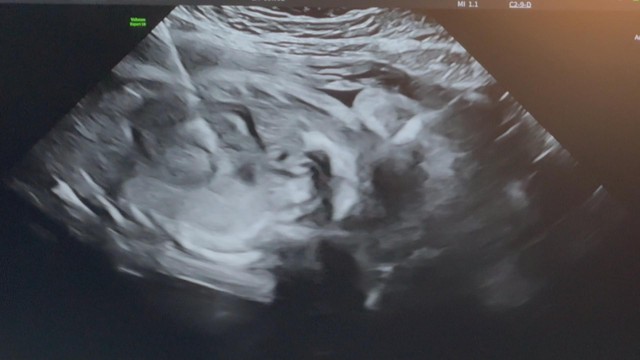

Hình ảnh siêu âm tim thai trong quá trình can thiệp bào thai tại Bệnh viện Từ Dũ

Đến 14 giờ ngày 14/10, ekip can thiệp bắt đầu phẫu thuật. Do thai nhi nằm sấp hoàn toàn, tư thế không thuận lợi cho việc tiếp cận tim, các bác sĩ quyết định thực hiện kỹ thuật xoay thai trong tử cung trước khi tiến hành thông tim. Sau 80 phút can thiệp, ca phẫu thuật kết thúc lúc 15 giờ 20 phút với kết quả thành công tốt đẹp.